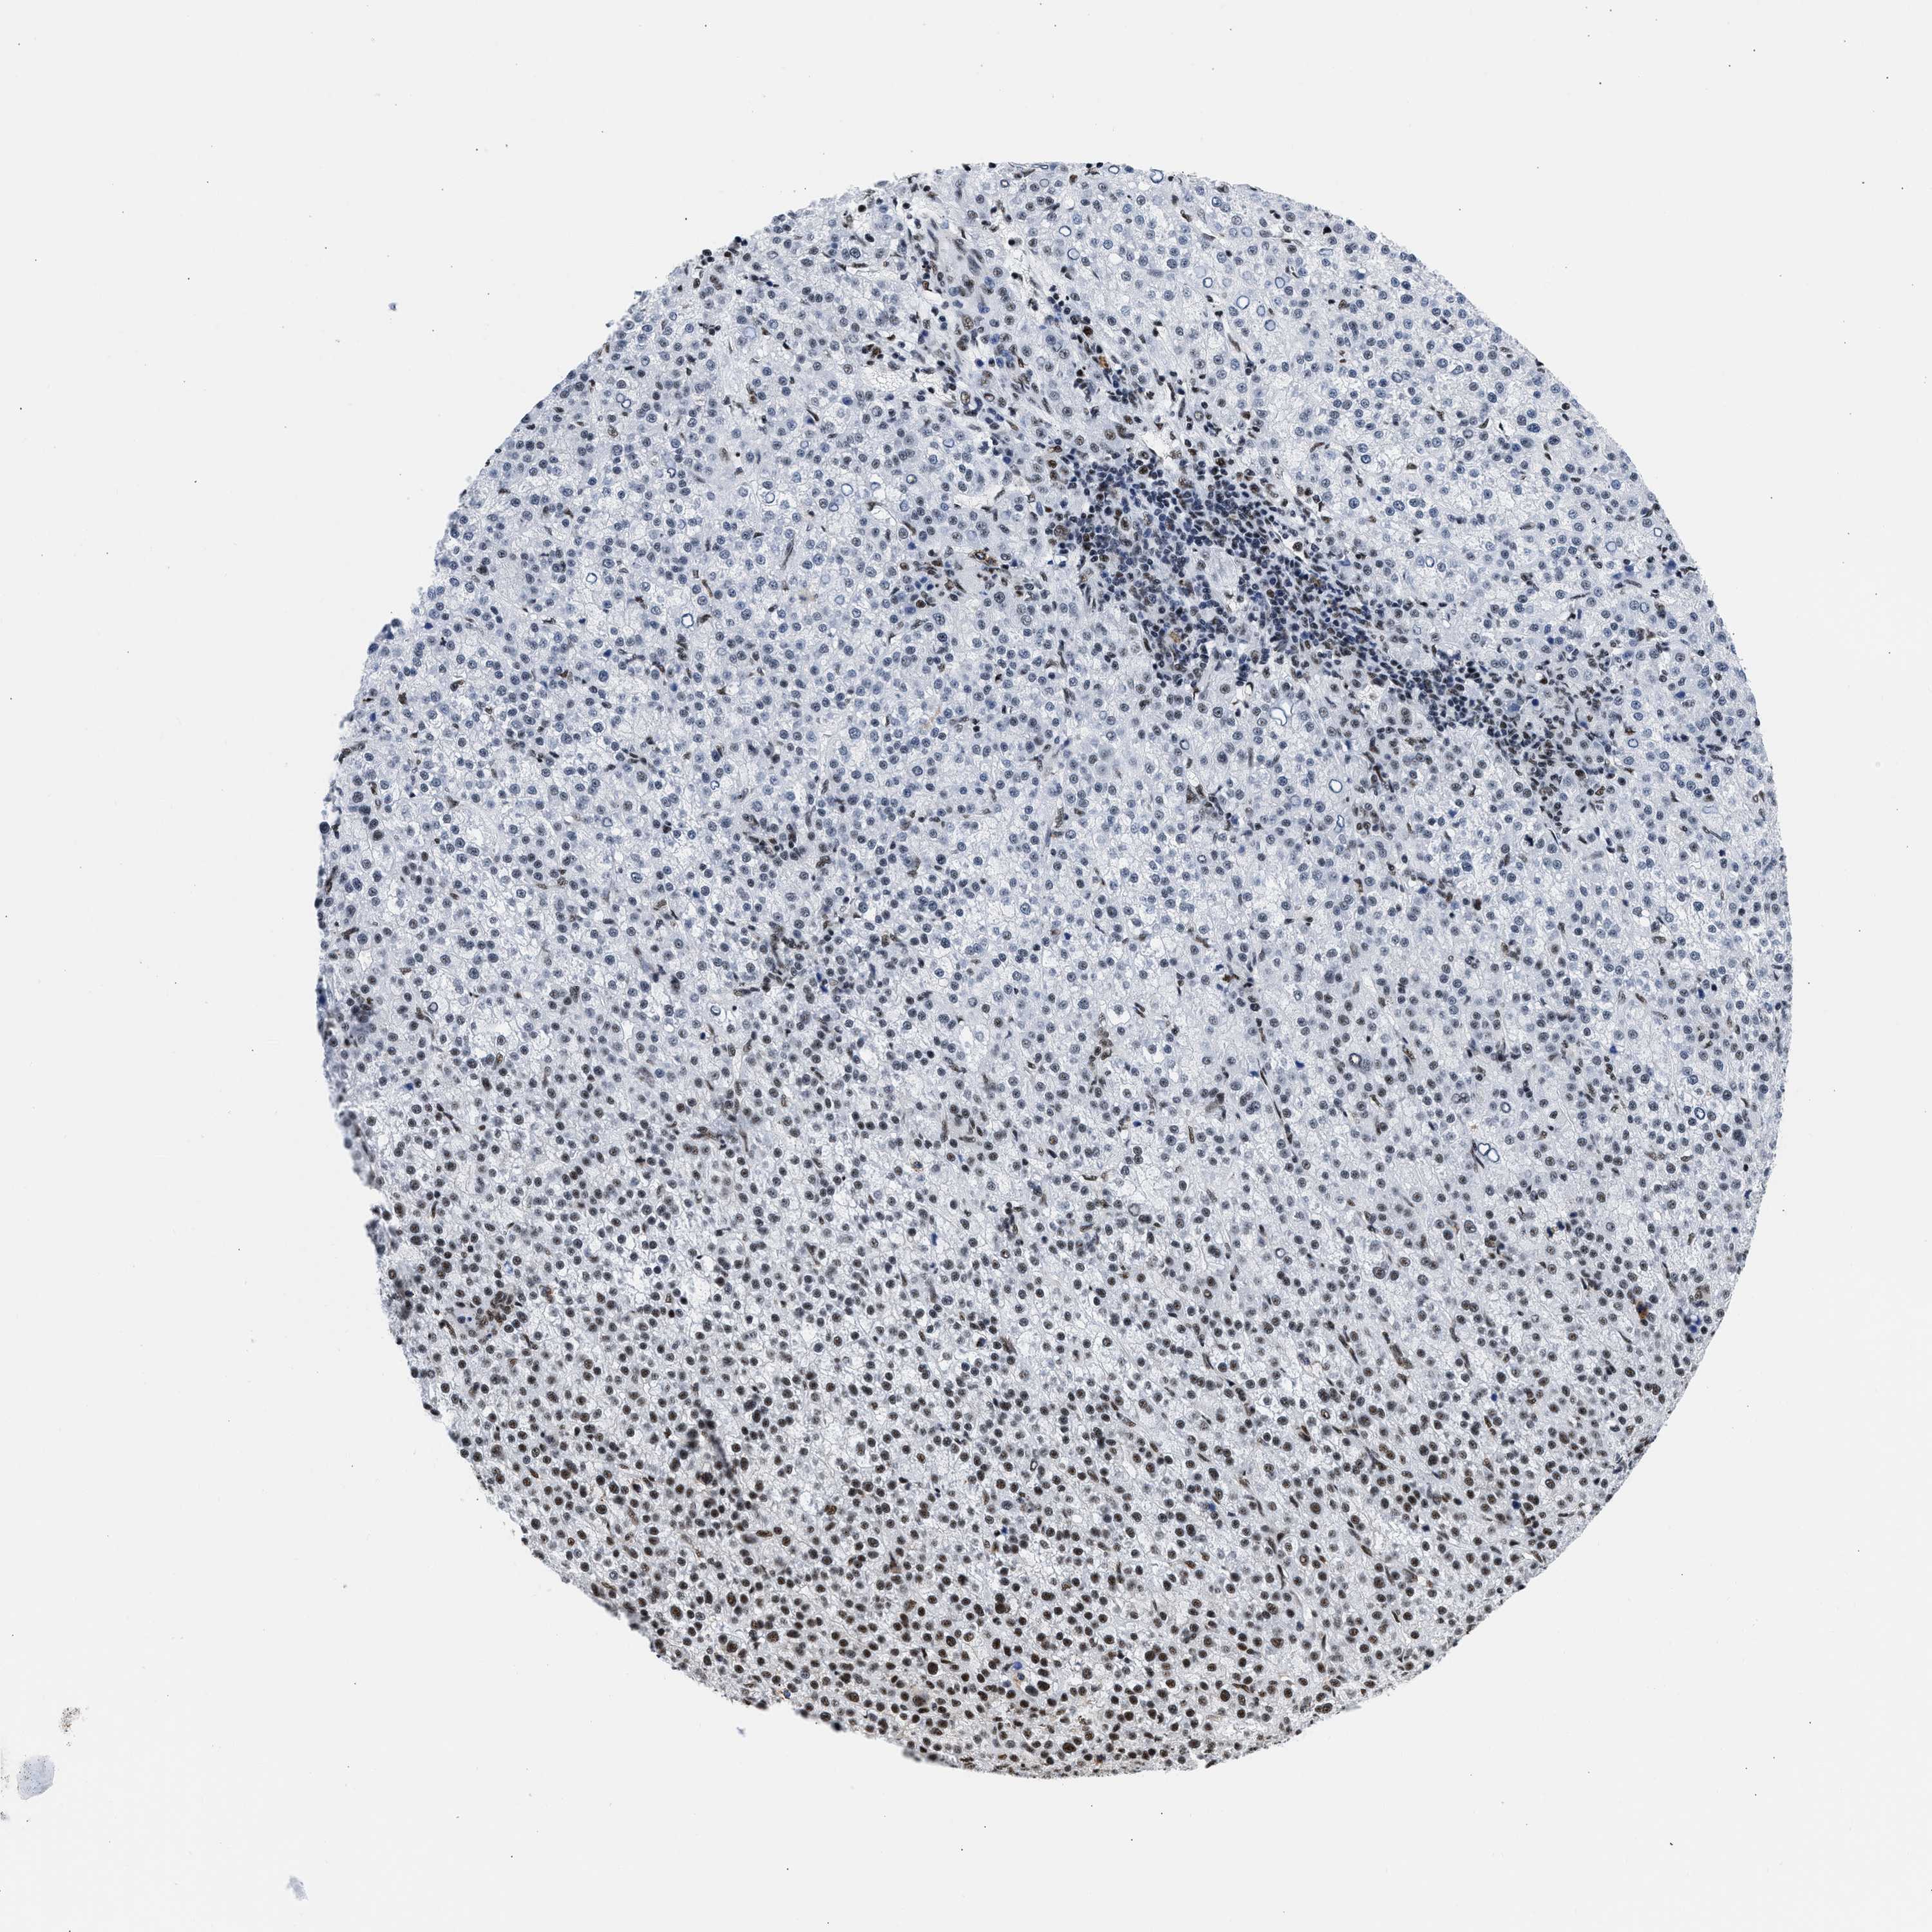

LIVER CANCER - Protein expressioni

A mouse-over function shows sample information and annotation data. Click on an image to view it in a full screen mode. Samples can be filtered based on level of antibody staining by selecting one or several of the following categories: high, medium, low and not detected. The assay and annotation is described here.

Note that samples used for immunohistochemistry by the Human Protein Atlas do not correspond to samples in the TCGA dataset.

Antibody stainingi

Antibody staining in the annotated cell types in the current human tissue is reported as not detected, low, medium, or high, based on conventional immunohistochemistry profiling in selected tissues. This score is based on the combination of the staining intensity and fraction of stained cells.

Each image is clickable and will lead to virtual microscopy that enables deeper exploration of all samples and also displays staining intensity scores, fraction scores and subcellular localization as well as patient and tissue information for each sample.

Antibody HPA018403

Staining

High

Medium

Low

Not detected

Intensity

Strong

Moderate

Weak

Negative

Quantity

>75%

75%-25%

<25%

None

Location

Nuclear

Cytoplasmic/membranous

Cytoplasmic/membranous,nuclear

Cholangiocarcinoma

Carcinoma, Hepatocellular, NOS